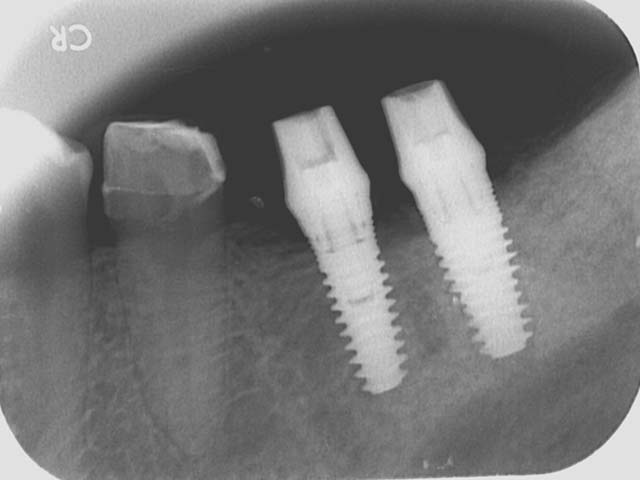

人工植牙 首頁 案例分享 人工植牙 前牙植牙 更多 牙橋嚴重蛀牙,即拔即種,避免二次傷口 更多 齒槽骨保存術+植牙 更多 前牙審美植牙 更多 微創植牙 更多 小臼齒植牙 更多 即拔即種 更多 鼻竇增高術(垂直)+植牙 更多 鼻竇增高術(側窗) 更多 «1»